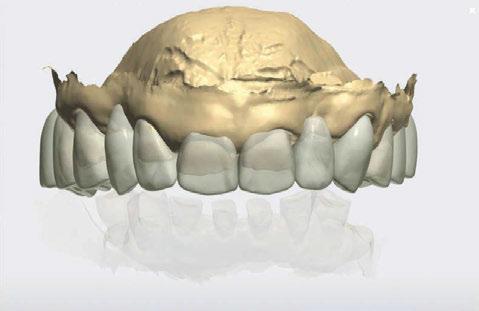

Figura 9. Propuesta de planificación maxilar con encerado diagnóstico digital. Se visualiza emergencia de los implantes y emergencia protésica con pilares angulados.

Figura 11. Encerado diagnóstico digital sobre maxilar superior.

Figura 10. Propuesta de planificación maxilar con encerado diagnóstico digital. Destaca la angulación del implante 1.6 esquivando el seno maxilar con un ángulo de inserción de 30 º y una emergencia protésica verticalizada.

Figura 12. Encerado diagnóstico digital teniendo en consideración un aumento de la dimensión vertical.

Figura 13. Representación gráfica de la futura colocación de los implantes y su relación con la rehabilitación.

16. Superposición radiológica implante 45 angulado, teniendo en consideración el encerado diagnóstico y preservando estructuras nerviosas.

Figura 14. Representación tridimensional. Destaca la protección de estructuras nobles (nervio mentoniano) al presentar un implante angulado con íntima relación.

Figura 15. Visión general tridimensional. Destaca la uniformidad en la disposición de los implantes. En amarillo emergencia implantológica y en gris emergencia protésica mediante pilares transepiteliales angulados multiplus.